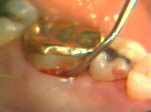

| Esta serie de

imágenes muestra el diagnóstico y tratamiento de la periodontitis

moderada en una mujer de 35 años de edad. Se observa

inflamación por el cambio de color, aspecto de la superficie y por la consistencia del margen gingival. Si el margen

gingival está flojo cuando aplicamos aire de la jeringa triple es una indicación de inflamación

del tejido. |

Note la

inflamación gingival y la presencia de placa supragingival en los

dientes. En bucal del segundo molar hay una bolsa profunda al

sondaje y placa supra y subgingival al movimiento lateral de la sonda. |